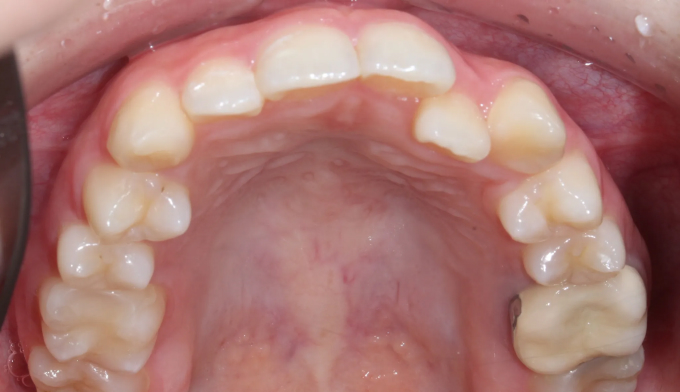

앞니 하나만 뒤로 들어간 경우, 해당 치아만 앞으로 빼내면 되는 간단한 교정이라고 생각하기 쉽습니다.

하지만 해당 치아가 뒤로 들어가면서 전체적인 치열이 한쪽으로 쏠리는 비대칭이 나타났기 때문에 이를 모두 해결하기 위해서는 전체교정을 통한 긴 치료기간이 필요합니다.

안쪽으로 들어간 앞니 양쪽으로 치열을 밀어서 공간을 확보해주고 앞니를 재위치 시켰습니다.

추가로 한쪽으로 틀어진 치열들도 위아래 중심선을 맞추어주었습니다.

총 치료기간은 17개월입니다.